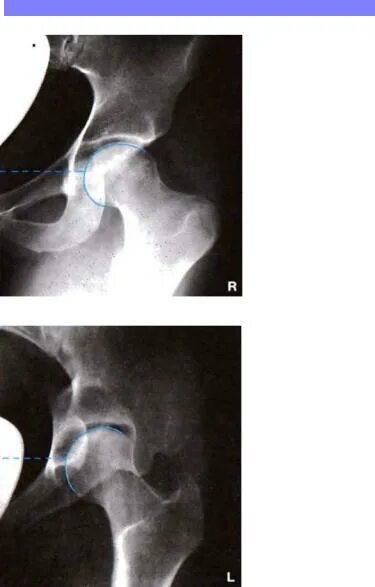

Рентген тазобедренный в двух проекциях